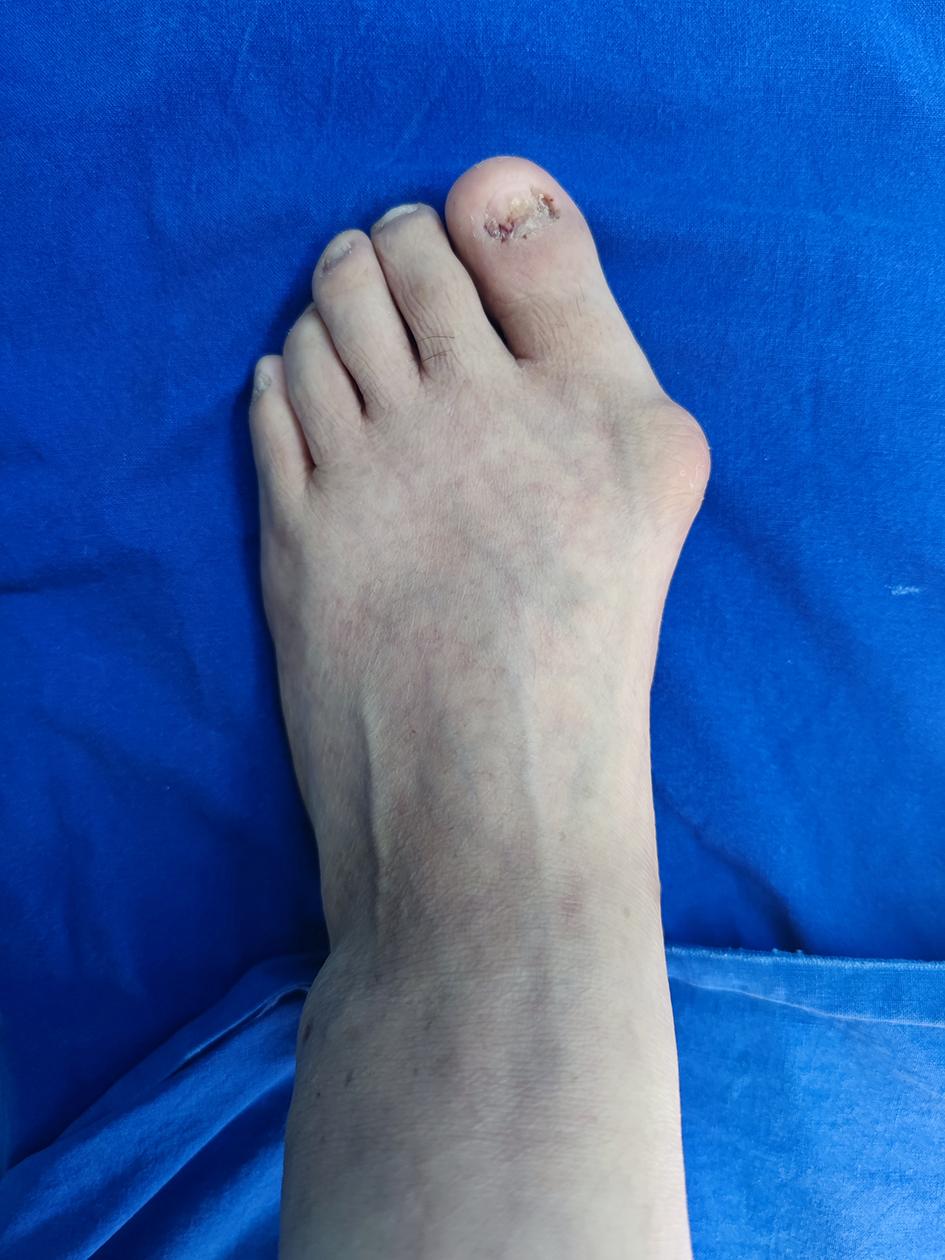

张阿姨,因双足拇外翻,长期受疼痛困扰,基本无法行走,既往老式手术,费用高,创伤大,让张阿姨一直无法下定做手术的决心。听闻普陀区人民医院足踝外科有新技术创伤小,恢复快,便慕名来普陀区人民医院就诊,医生查看张阿姨双足后,便收治入院。

入院后,经过X片下的测量和术前相关检查后,与张阿姨进行手术沟通,拟定手术方案,最终决定针对张阿姨的情况给予拇外翻矫形术。

术后张阿姨姆囊部的疼痛及行走疼痛明显缓解,经过一段时间的休养,现已可以自由行走。“感谢你们让我彻底摆脱了拇外翻对我造成的多年困扰,现在我可以出门买菜,跳跳广场舞了”张阿姨握着医生的手激动的说。科普小知识